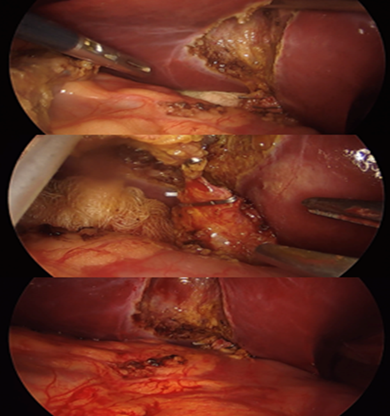

Figure 2: Per-operative view of laparoscopic cholecystectomy. No

complications or adverse event were observed intra-operatively

We present the case of a 30-year-old female,

pancreatitis (Figure 1) 2 months prior to a laparoscopic cholecystectomy

(LC) (Figure 2).